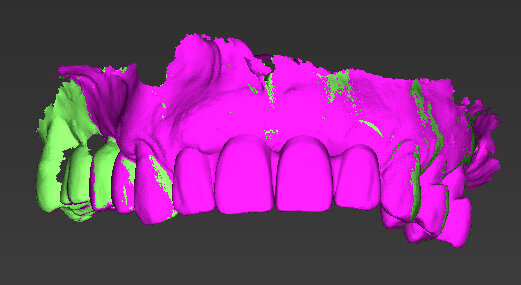

Il piano di trattamento prevede l’estrazione degli elementi dentali, l’inserimento di due impianti e la realizzazione di una protesi fissa di quattro elementi. Il problema da gestire è quello della fase provvisoria. Non è ipotizzabile una protesi mobile e quindi programmiamo di inserire subito dopo l’intervento un provvisorio immediato. Questo ci consente di condizionare da subito i tessuti periimplantari e anche le zone dei ponti. Si rileva un’impronta digitale (Figg. 5, 6), e la programmazione degli impianti viene effettuata con un software di chirurgia guidata (Fig. 7) e la posizione degli impianti nello spazio biologico e nello spazio protesico viene fatta sulla base di una ceratura diagnostica (Figg. 8, 9). Inseriamo gli impianti virtuali nell’osso disponibile (Figg. 10-13) e in relazione all’aspetto protesico correggiamo l’asse di inclinazione degli impianti con componenti secondarie angolate a 17° (Figg. 14, 15). Questo ci consentirà di realizzare una protesi avvitata con i fori situati nella zona palatale.

Fig. 7 - Sovrapposizione del File PLY della ceratura e dei tessuti.

Fig. 8 - Ceratura diagnostica.

Fig. 9 - Visione occlusale ceratura.